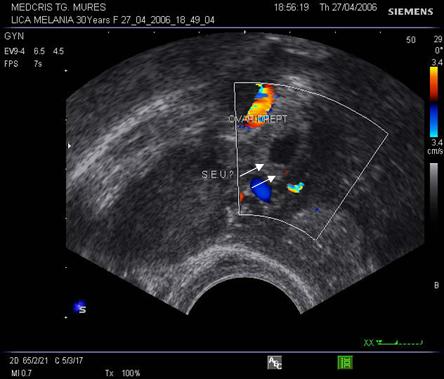

Fig nr 52

Langa ovarul drept ( cu sageata lunga ) se observa o formatiune ovalara cu ecou

hipoecogen central, sarcina extrauterina la 5 sapt. si 3 zile de amenoree ( doua sageti )

Fig nr 53 Aceeasi sarcina extrauterina ca in figura precedenta, se evidentiaza coroana trofoblastica la ecoul doppler color si se schiteaza vezicula vitelina ( cu sageata )